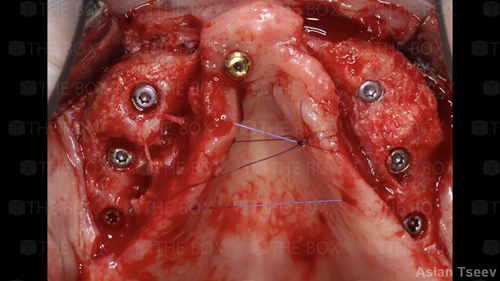

A new case was made public by Jean-Claude Imber check it out here.